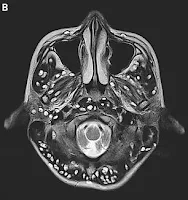

An MRI scan showed the patient had numerous cysts in his cerebral cortex - the outermost layer of the brain, which is responsible for thinking and processing information collected via our five senses.